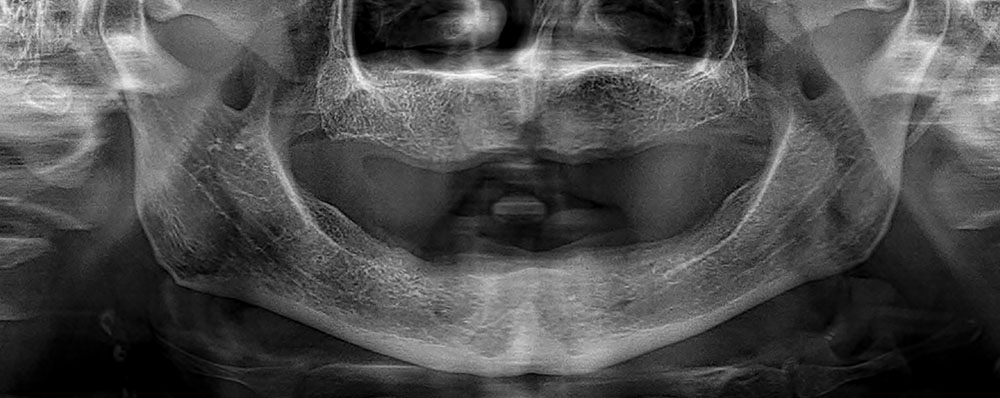

The full mouth dental implant procedure typically involves several steps and multiple visits to the dentist over the course of several months. The process typically begins with a comprehensive evaluation, including X-rays, CT scans, and a thorough examination of your oral health, to determine the best course of treatment.